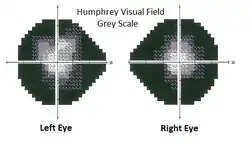

Visual field testing

Measurements of visual field defects can be done by visual field testing. It can be performed by various methods, including confrontation technique, amsler grid, tangent screen, kinetic perimetry, or static perimetry. Cost common is automated perimetry.

Perimetry

Visual field assessment encompasses various perimetry techniques used in ophthalmology to evaluate how well someone can see in different areas of their vision. These techniques include flicker perimetry, which assesses temporal visual function and spatial resolution targeting the M pathway; Frequency Doubling Technology (FDT), which utilizes an optical illusion to evaluate ganglion cell damage within the M pathway; Short-Wavelength Automated Perimetry (SWAP), isolating the S cone system to detect early glaucoma-related damage; High-pass Resolution Perimetry, focusing on resolution over the central visual field; Saccadic Vector Optokinetic Perimetry (SVOP), using eye tracking for assessing natural eye movements; and various standard and automated perimetry methods like Goldmann, Humphrey field analyzer, and Octopus, each employing different techniques for visual field assessment. These diverse methods aid in diagnosing and monitoring ocular conditions, offering valuable insights into visual function and pathology.[5][29][30]

Modern computerized perimeters like humphrey field analyser (HFA) give more comprehensive and accurate reports than finger testing methods.